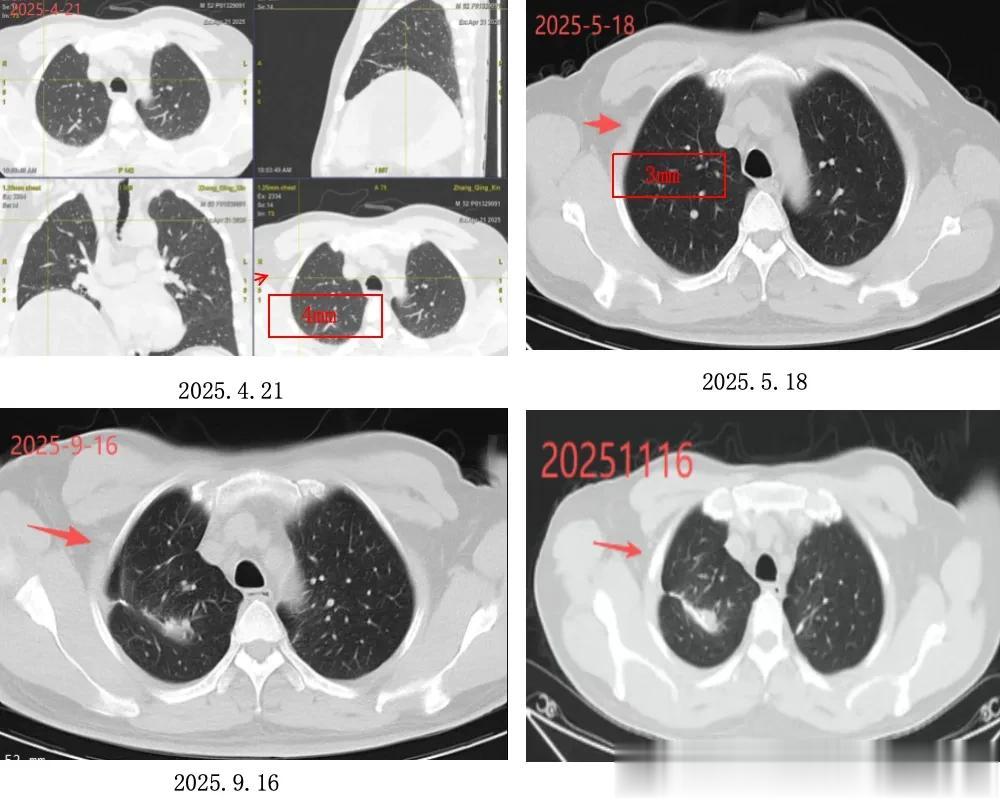

▶ 肺部病变:右肺上叶术后改变,索条影稳定,无新增活性病灶;

影像表现:2025.4.21PET-CT示:右肺上叶结节,大小约4mm,代谢不高,随访;2025.5复查示:右肺上叶结节,大小约3mm;2025.9至2025.11.16复查示:右肺上叶术后改变,可见索条影。